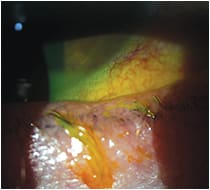

This patient presented wearing a monthly contact lens and complained of discomfort and having to remove his contacts after six hours of wear. He was diagnosed with meibomian gland dysfunction and dry eye and was prescribed lid hygiene QD, warm compresses QD, Omega’s PO, artificial tears PRN, cyclosporine BID OU, and a combination topical steroid/antibiotic drop BID OU x 2 weeks. After treating the meibomian gland disease and dry eye for four weeks, he was then refit in a daily contact lens, giving him better comfort and increased wear time.